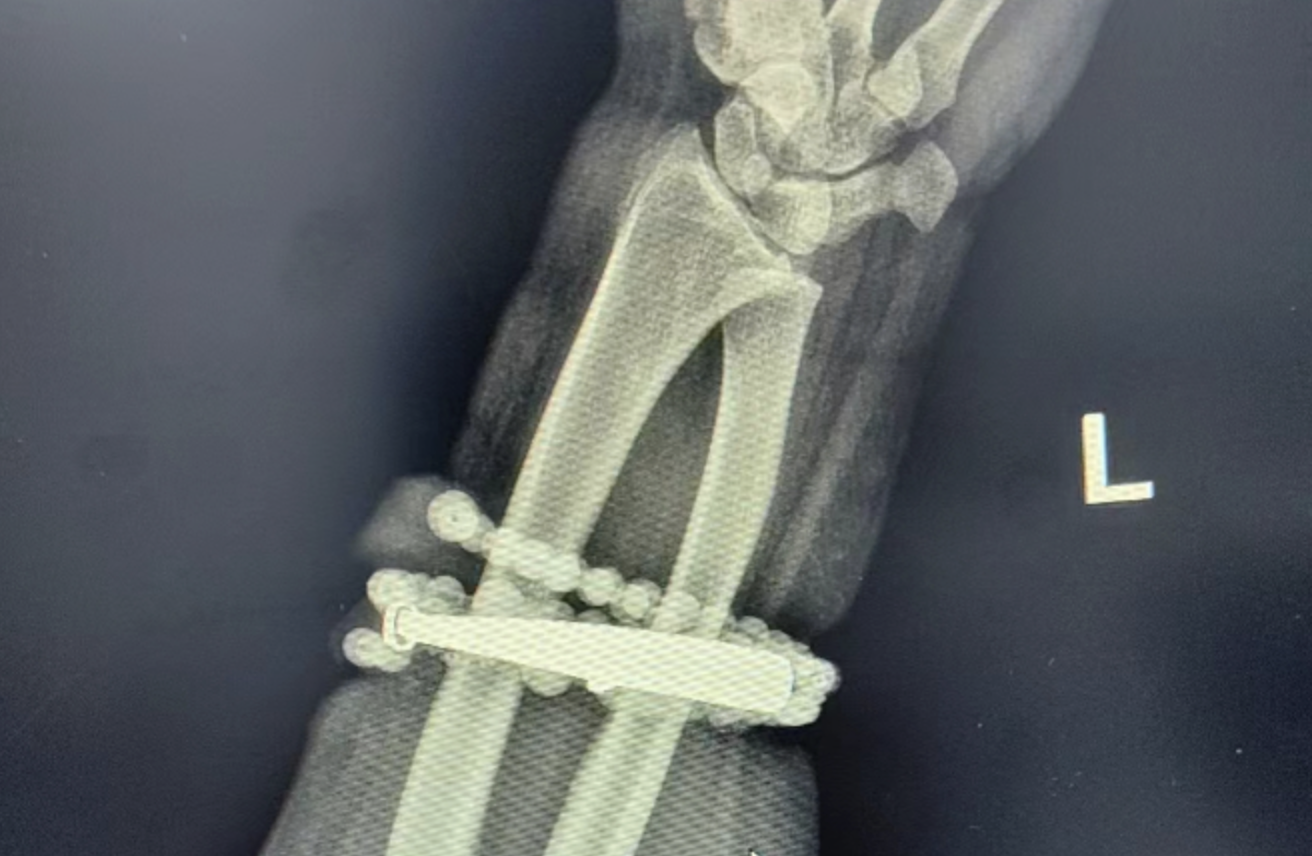

然而兩週前情況惡化,手腕疼痛劇烈,甚至紅腫化膿。龔姓女子仔細檢查才驚覺手鐲與串珠部分已嵌入皮肉,無法自行取下,這才前往醫院求診。

醫師檢查後指出,龔姓女子因首飾長期壓迫與摩擦,加上細菌感染,引起慢性發炎與肉芽組織增生,手鐲已形成人體異物刺激,造成局部持續感染。若未及時治療,感染可能擴散,嚴重恐威脅生命或導致手部功能受損。

經約一小時手術處理,醫師順利將手鐲及串珠從增生組織中剝離,並進行清創與引流。龔姓女子術後狀況穩定,目前已康復出院。